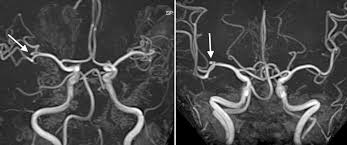

③ MRA(자기공명혈관조영술): 뇌혈관의 흐름과 동맥류 유무를 평가합니다.

(2) 침습적 검사

① 뇌혈관조영술(DSA): 가장 정확한 검사로, 동맥류의 위치, 크기, 형태를 정밀하게 파악할 수 있습니다. 치료 계획 수립에 중요한 역할을 합니다.